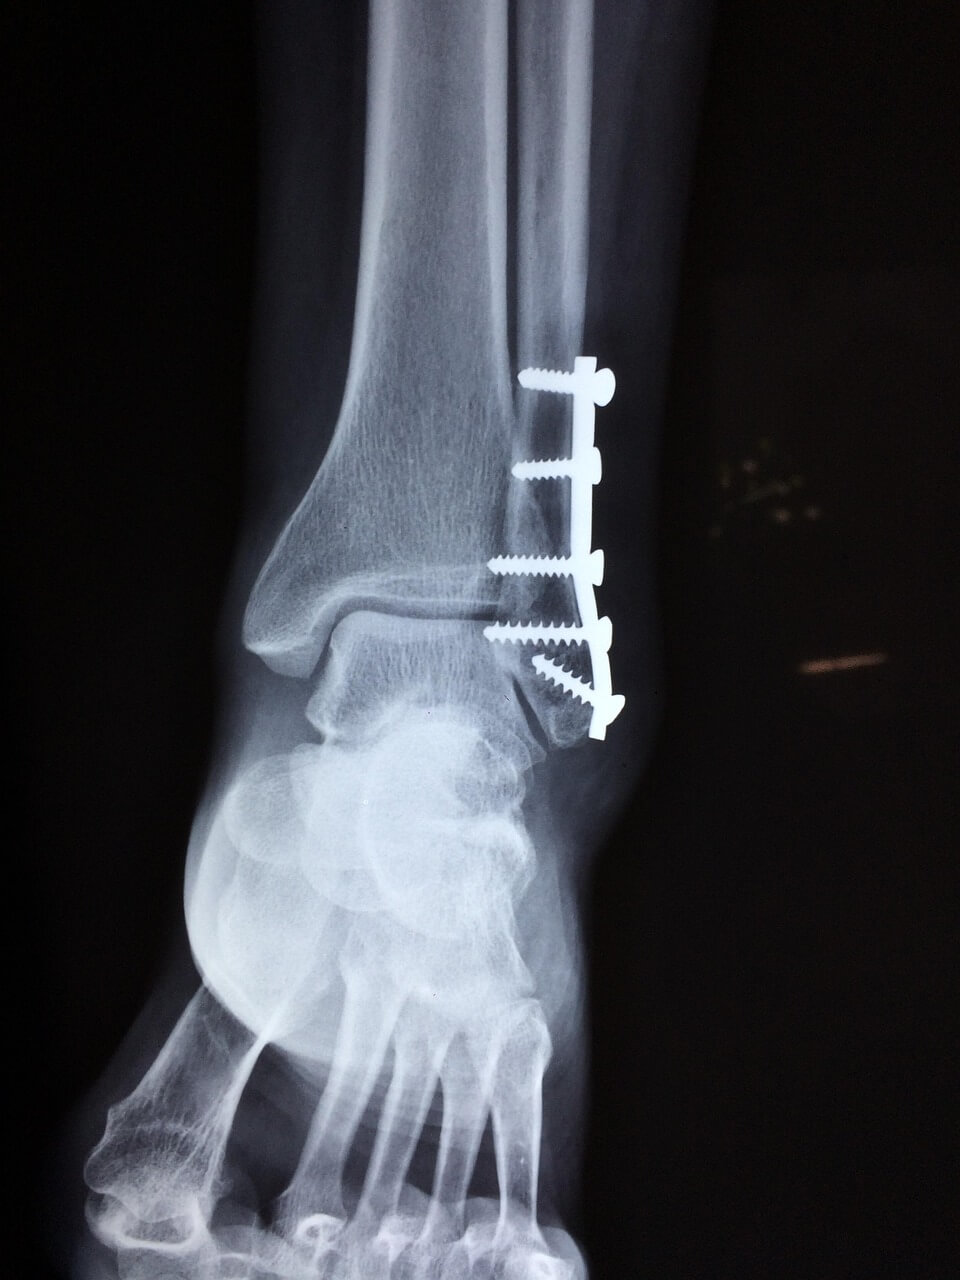

많은 사람들이 발목 염좌와 골절을 혼동합니다. 염좌는 일정 시간이 지나면 보행이 어느 정도 가능하지만, 골절은 체중 부하 자체가 불가능하고 뼈의 모양이 변형될 수 있습니다. 정확한 구분을 위해서는 X-ray나 MRI 검사가 필요합니다.

- X-ray: 골절 여부를 확인하는 기본 검사.

- MRI: 인대 파열 정도, 연골 손상 여부를 정밀하게 확인.

- 초음파: 실시간으로 인대 상태를 관찰할 수 있으며, 재활 단계 평가에도 유용합니다.

발목 염좌는 골절이나 연골 손상과 함께 동반되는 경우가 있어, 단순한 ‘삐끗함’으로 단정하지 말고 정확한 검사가 필요합니다.